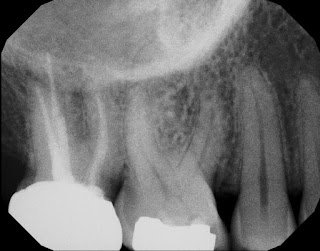

One of the many uses of CBCT is to help us determine the depth of a crack – seen on the occlusal surface of a tooth, but uncertain as to how deep it goes down the root. Obviously the deeper the crack goes below the CEJ, the poorer the long term prognosis.

CBCT shows a narrow, bony defect identifying a crack in the axial (Z) view. The sagittal (Y) view shows the depth of the crack. A new crown would have to go past this depth to cover the crack up. This view helps us make a determination of the restorability of the tooth.

In this case, the crack would never be completed removed or covered up by the crown making the long term prognosis poor. CBCT allows us to make this evaluation without having to remove the amalgam filling and chase the crack – saving the patient (and us) time and money.